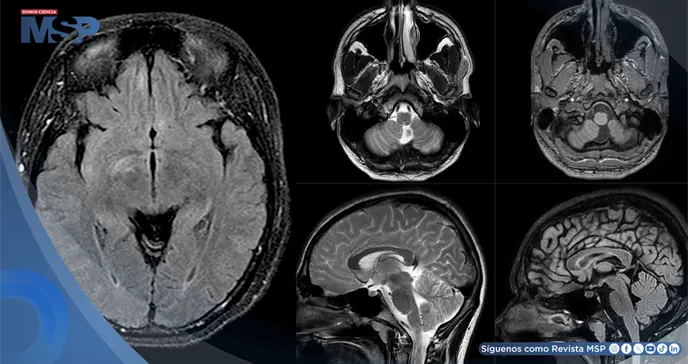

La tomografía computarizada (TC) craneal inicial reveló una hemorragia cerebelosa izquierda. Durante su hospitalización, la paciente desarrolló una pérdida de visión central en el ojo derecho, que describió como un círculo negro. Una resonancia magnética (RM) cerebral confirmó la sospecha clínica al mostrar un realce del nervio óptico derecho, sugestivo de un proceso desmielinizante agresivo.

El estudio se complementó con RM de la columna cervical y torácica, que evidenció un proceso desmielinizante medular central continuo. Con estos hallazgos, la sospecha de un síndrome desmielinizante primario era alta. Se inició tratamiento con metilprednisolona y, de manera crucial, el título de anticuerpos contra la Acuaporina-4 (AQP4), también conocidos como anticuerpos contra la Neuromielitis Óptica (NMO), resultó positivo tras el alta.

Una nueva RM cerebral mostró focos de hiperintensidad en T2 en regiones como el núcleo caudado derecho y los lóbulos frontales y temporales mediales. El análisis del líquido cefalorraquídeo (LCR) fue determinante: mostró una tasa elevada de síntesis de IgG y, lo que es más significativo, fue positivo para anticuerpos contra el receptor de NMDA. Este hallazgo permitió establecer el tercer diagnóstico: encefalitis anti-NMDAR. La paciente fue tratada con plasmaféresis, con lo que la encefalopatía se resolvió y la neuroimagen mostró mejoría.

Una TC craneal mostró una pérdida difusa de volumen cerebral. Tras el alta, un examen fisioterapéutico reveló que había perdido la capacidad de mover o sentir las extremidades inferiores. Una resonancia magnética de la columna vertebral confirmó una nueva lesión desmielinizante activa, indicando una exacerbación de la NMO.